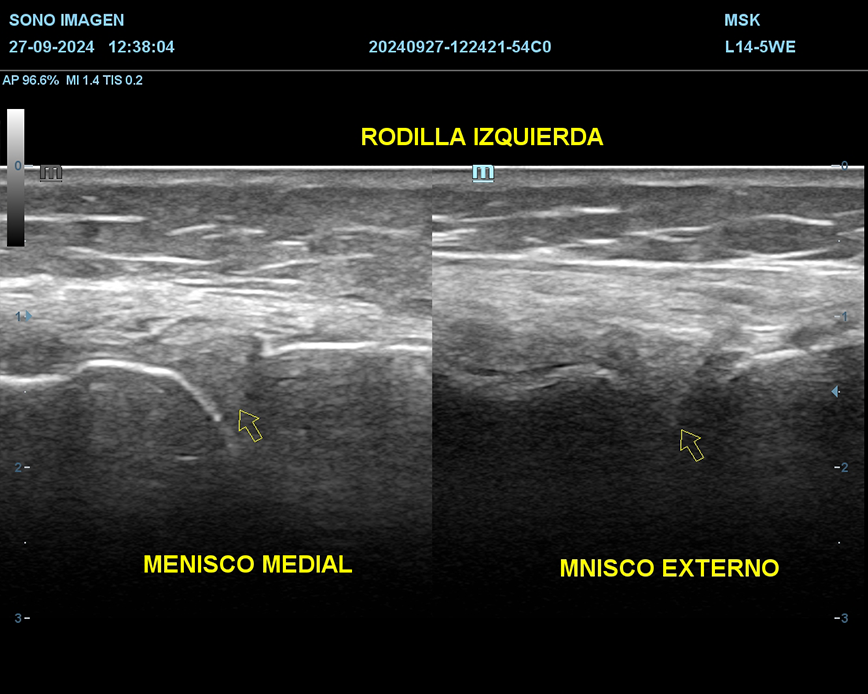

Ecografía de rodilla

- evaluación del dolor de rodilla

- lesiones de tejidos blandos: tendinosis, desgarros ligamentosos, rupturas meniscales.

- derrame articular

- inflamación o infección

- evaluación de lesiones deportivas

- quiste de Baker

- seguimiento postoperatorio

- traumatismos